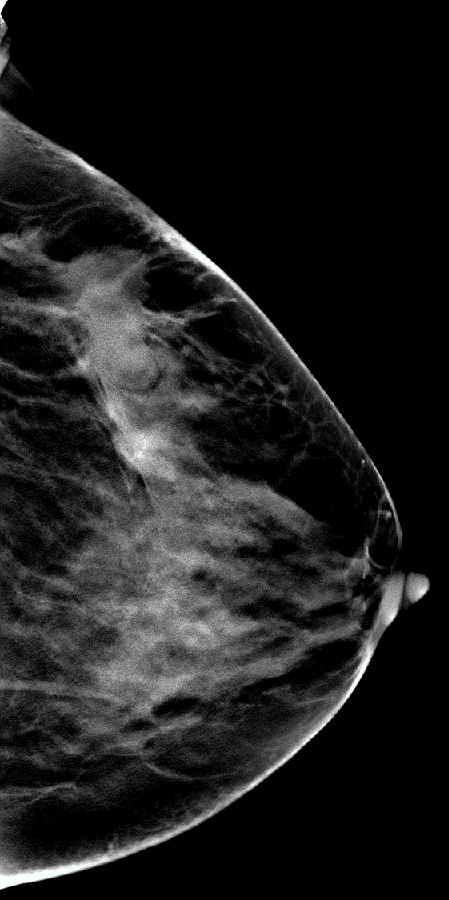

V-preview图像: